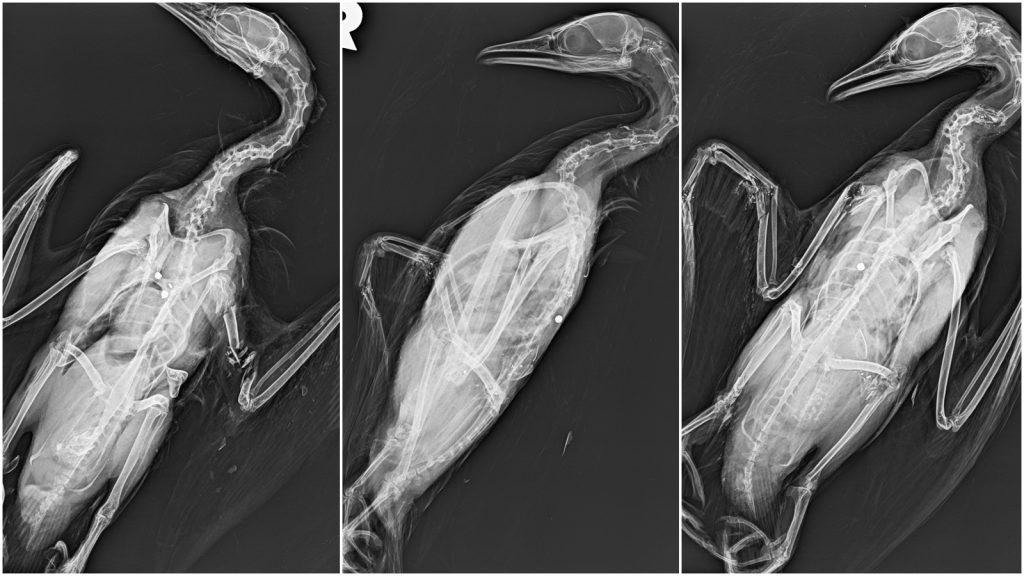

A Nébih laboratóriumába érkezett, Tassról származó kis kárókatona-tetemek vizsgálatával lövedék okozta vérzéssel kísért traumás elváltozásokat és következményesen a vérkeringés heveny összeomlását diagnosztizálta a hivatal

– írták a Pecaverzumnak küldött közleményükben.